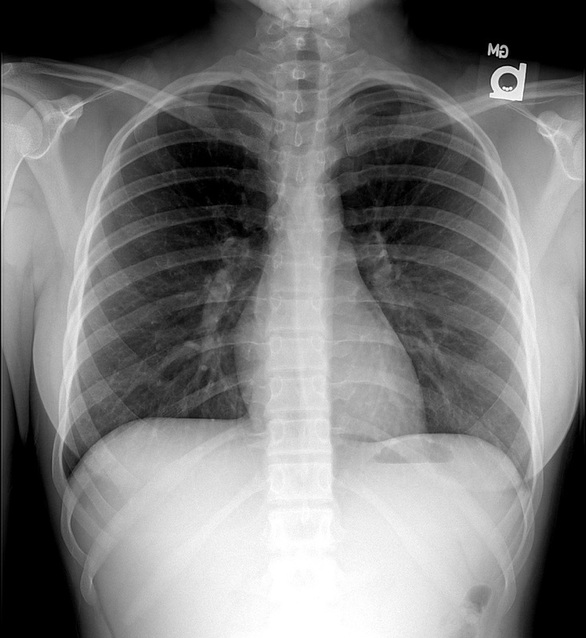

13 year old female.

1.  What is the key finding.